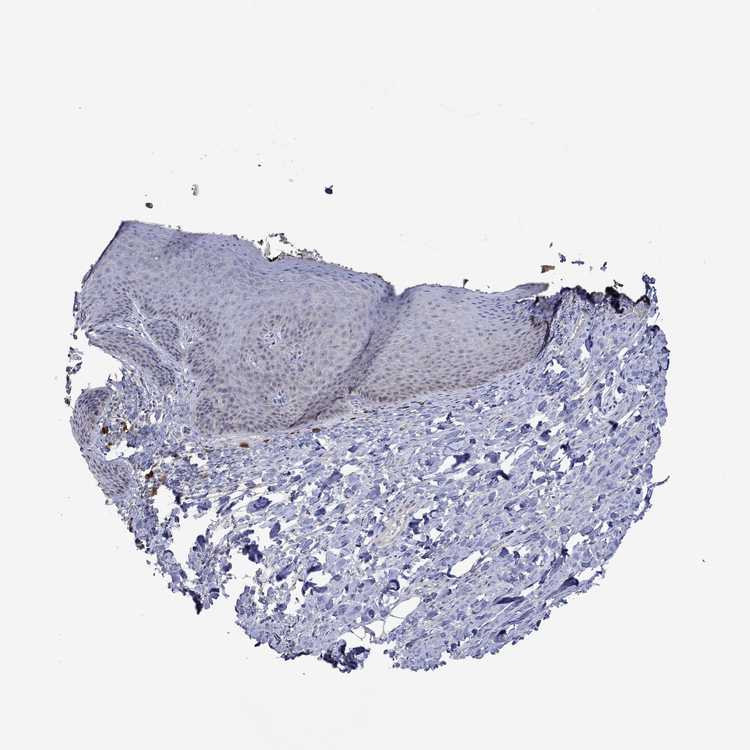

SKIN 2 - Antibody stainingi

Antibody staining in the annotated cell types in the current human tissue is reported as not detected, low, medium, or high, based on conventional immunohistochemistry profiling in selected tissues. This score is based on the combination of the staining intensity and fraction of stained cells.

Each image is clickable and will lead to virtual microscopy that enables deeper exploration of all samples and also displays staining intensity scores, fraction scores and subcellular localization as well as patient and tissue information for each sample.

Antibody HPA043337Antibody HPA048310Antibody HPA069148

Epidermal cells MediumNot detectedNot detected